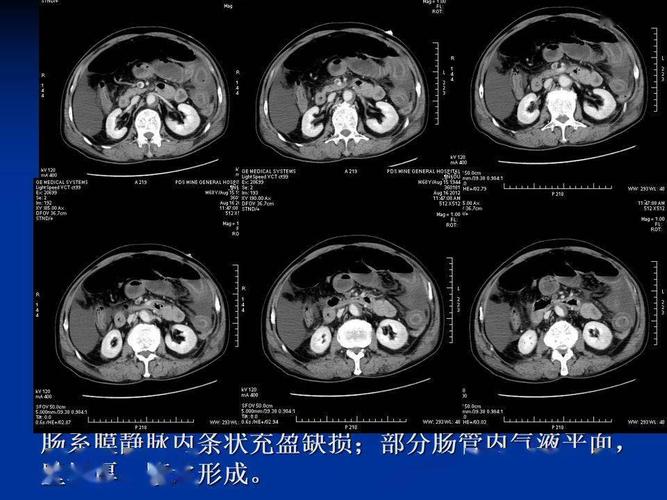

肠梗阻片子,肠梗阻ct

详细肠梗阻的分类及影像学表现高清图片文字讲解

高清图片文字讲解肠梗阻的分类及影像学表现

肠梗阻ct